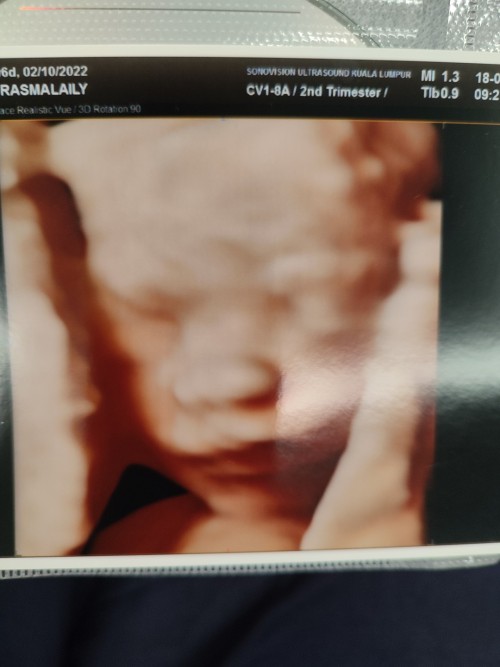

Detail scan

Hai ibu2..nak tnya..detail scan penting x.?? Kalau x buat detail scan xpe ke.?? Ade ke yg x buat detail scan.?? #firstbaby #firstmom

Kena buat at least sekali.. sy suggest cuba utk buat juga sbb apa2 masalah dgn baby then boleh prepare mentally,financially if anak ada apa2 kecacatan..rujukan ke certain pakar boleh dibuat awal sebelum bersalin lg..scan ni buat masa beginning 3rd trimester.. waktu tu baby dh besar sikit utk appreciate baby’s details..buat utk detect masalah kongenital (spinal bifida,hydrocephalus,down’s syndrome etc).proper detailed scan mahal,buat appointment dgn pakar di private,kalau kt clinic,doktor biasa je yg buat.. Husband sy ada history of spina bifida among his siblings,who passed away right after birth so sy minta rujukan ke pakar utk detailed scan..so sepanjang pregnancy sy,4 kali appointment detailed scans semua normal..done everytime by fetomaternal consultant.lps 1st scan normal,boleh je sy xcontinue follow up but since diberi tarikh and consultant sendiri yg buat scan jadi sy pergi je everytime..klu buat private pun,mungkin doktor biasa/pakar sahaja yg buat scan,better my scan to be done by consultant.. Beza tau detailed scan ni,scan tgk byk details yg xdibuat masa follow up biasa di kk/private..sekali detailed scan sy akan ambil masa 1j-1 1/2j utk case normal mcm sy..tgk dari physical details mcm ear,nose,mouth,hands,fingers,legs,toes,body,tulang belakang dan punggung (esp ni spina bifida case).then tgk details major blood vessels mcm uterine arteries,umbilical arteries,cerebral arteries dlm kepala..jantung,paru2,kidneys..ukur lilit kepala,panjang tulng femur,size badan (abdominal circumference),lebar kepala (biparietal diameter) etc